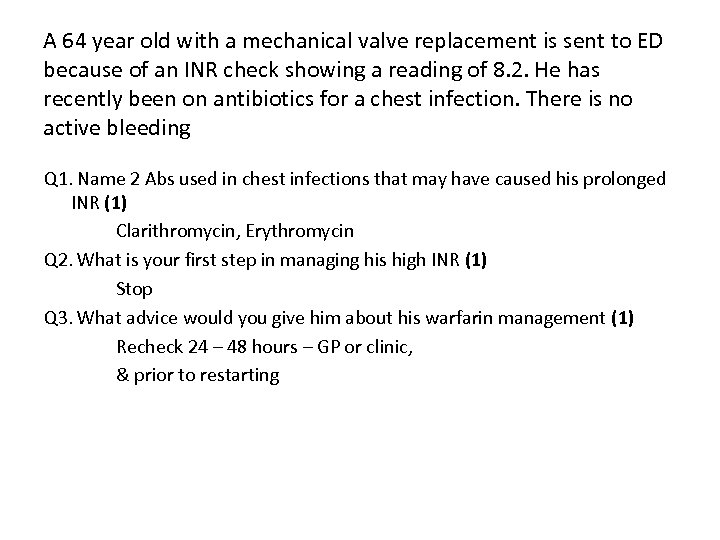

A 64 year old with a mechanical valve replacement is sent to ED because of an INR check showing a reading of 8. 2. He has recently been on antibiotics for a chest infection. There is no active bleeding Q 1. Name 2 Abs used in chest infections that may have caused his prolonged INR (1) Q 2. What is your first step in managing his high INR (1) Q 3. What advice would you give him about his warfarin management (1)

A 64 year old with a mechanical valve replacement is sent to ED because of an INR check showing a reading of 8. 2. He has recently been on antibiotics for a chest infection. There is no active bleeding Q 1. Name 2 Abs used in chest infections that may have caused his prolonged INR (1) Clarithromycin, Erythromycin Q 2. What is your first step in managing his high INR (1) Stop Q 3. What advice would you give him about his warfarin management (1) Recheck 24 – 48 hours – GP or clinic, & prior to restarting